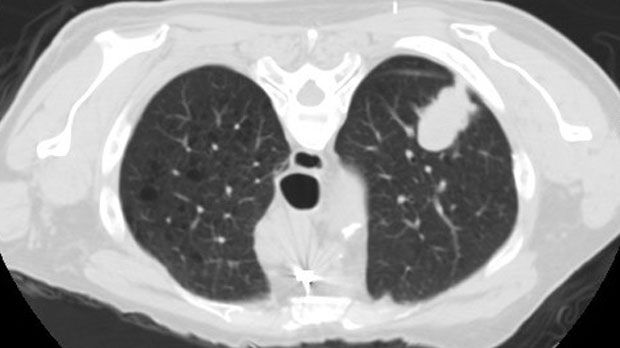

CT Scan

A CT scan (computed tomography) of the chest is performed to provide detailed, cross-sectional images of the lungs, airways, and surrounding structures that cannot be seen on a standard X-ray. It is commonly used to evaluate lung nodules, scarring, infections, blood clots, inflammation, and other complex pulmonary conditions, as well as to monitor known lung disease over time. During the scan, you will lie comfortably on a table that moves through the CT scanner while a series of images are taken; the test is painless and typically takes only a few minutes. In some cases, contrast dye may be used to enhance image clarity, and you will receive instructions beforehand if this is needed. After the scan, you can usually return to normal activities right away, and the images are reviewed to help guide diagnosis and treatment planning.